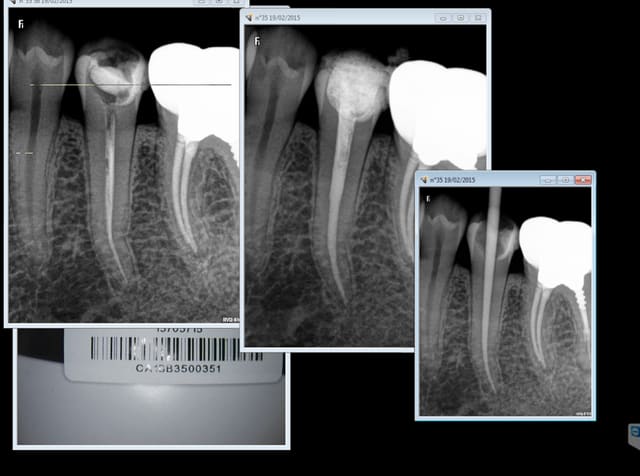

Capture d e cran 2015 02 17 19.37 - Eugenol

Capture d e cran 2015 02 19 17.45 - Eugenol